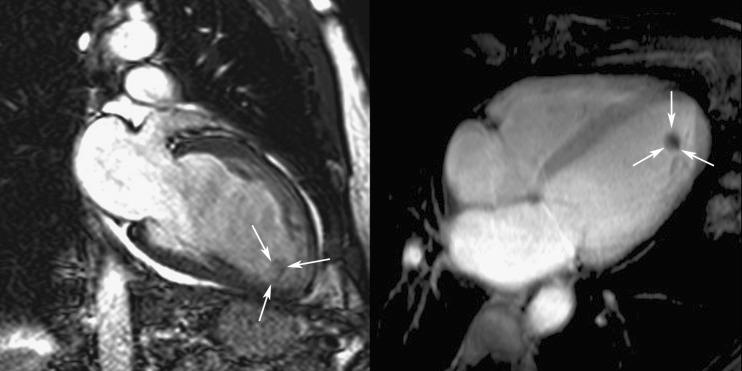

The emerging role of magnetic resonance imaging and multidetector computed tomography in the diagnosis of dilated cardiomyopathy.

Magnetic resonance imaging and multidetector computed tomography are new imaging methods that have much to offer clinicians caring for patients with dilated cardiomyopathy. In this article we briefly describe the clinical, pathophysiological and histological aspects of dilated cardiomyopathy. Then we discuss in detail the use of both imaging methods for measurement of chamber size, global and regional function, for myocardial tissue characterisation, including myocardial viability assessment, and determination of arrhythmogenic substrate, and their emerging role in cardiac resynchronisation therapy. ELECTRONIC SUPPLEMENTARY MATERIAL: The online version of this article (doi:10.1007/s13244-011-0101-8) contains supplementary material, which is available to authorized users.